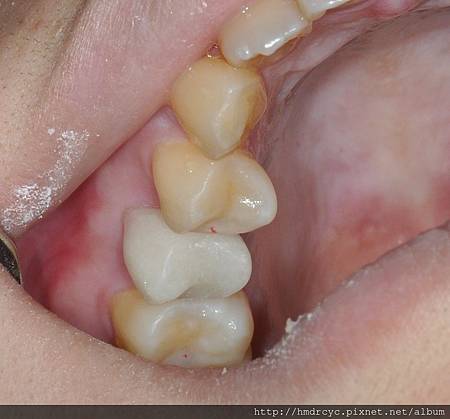

印模完成鑄心後 裝置到牙齒內

當次就可以裝上臨時假牙

當後續假牙要製作全瓷牙冠時

鑄心的選擇就不一樣

為了不讓金屬顏色透出來影響美觀

欣美牙醫推薦選擇鑄造陶瓷鑄心